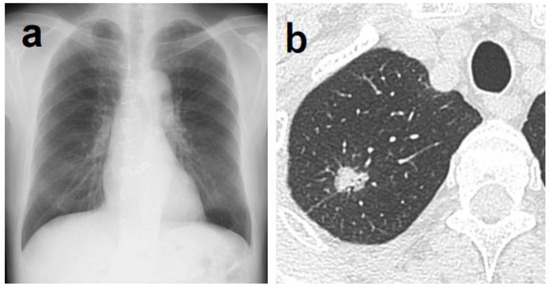

The main reasons why lung tumors could not be detected by the AI in 84 cases are listed in Table 2. Thirty-five cases had lesions overlapping with anatomical structures, such as the mediastinum, heart, and clavicle, or lesions below the diaphragm. Eight of these 35 cases were detectable by physicians (Figure 1). Conversely, there was one case in which it was difficult for physicians to detect the shadow overlapping the anatomical structures, but it was detected by AI (Figure 2). Eighteen cases were AIS, thirteen were lepidic adenocarcinoma (invasive size: 0.05–2.0 cm), and six were small nodules less than 0.7 cm in diameter. The other six cases were difficult to visualize on chest radiographs. Of these six cases, three cases had ground-glass components as the main component on CT, and one case had nodule and pulmonary vessels visible in succession. Many of these lesions were difficult to visualize due to the imaging conditions. Six patients did not fit these conditions; their lesions could be determined by physician interpretation, and their non-detection was judged to be an oversight by the AI (Figure 3).

Figure 2. (a) Although it was difficult for physicians to determine the abnormal shadow, AI was able to highlight a shadow overlapping the clavicle in the right upper lung field. (b) Chest CT showing a nodule with a total and solid size of 1.6 cm in the right S1 region. The histopathological diagnosis was adenocarcinoma (papillary adenocarcinoma), total tumor and invasive size of 1.8 cm, pT1bN0M0 (stage IA2).